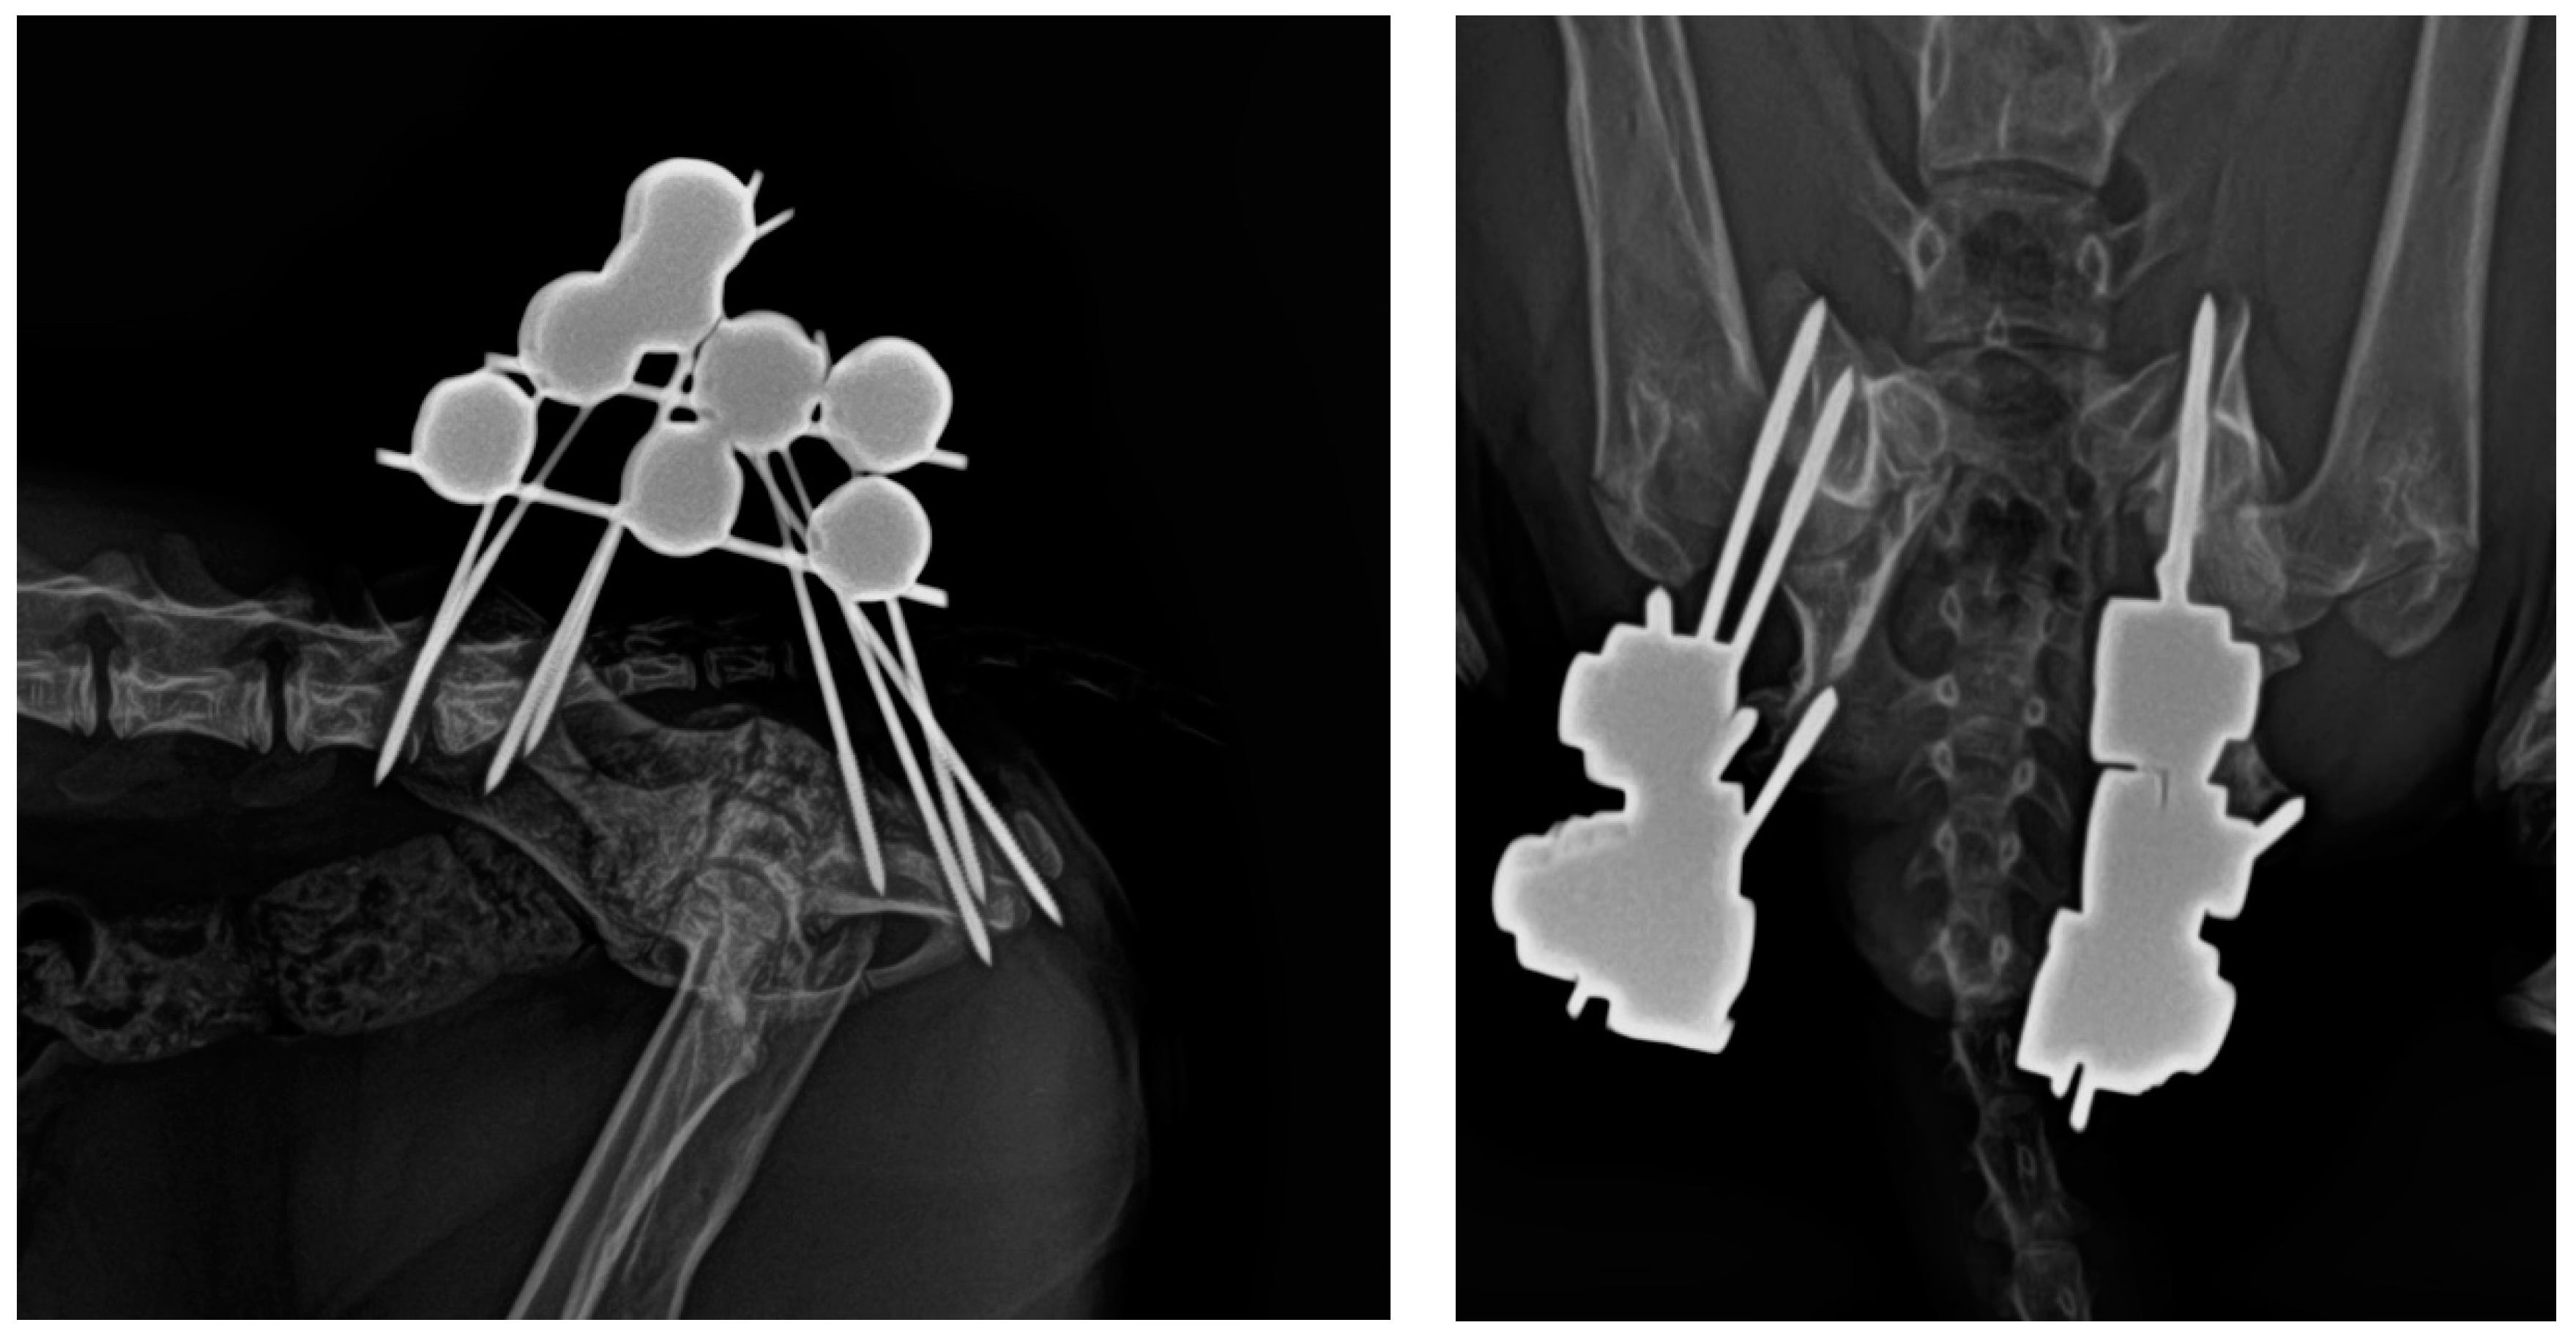

2.2. Surgical Technique

- Sacral tuberosity corridor of the ilium, near the origin of the gluteus medius muscle. The pins were inserted at an angle of 10–15° from proximo-medial to disto-lateral to the vertical.

- Corridor of the body of the ilium, in the caudal aspect, along the origin of the gluteus profundus muscle, with pins inserted at an angle of 10–15° to the vertical of the iliac crest.

- Ischial tuberosity corridor, with pins inserted at an entry angle of 10–15° to the vertical.